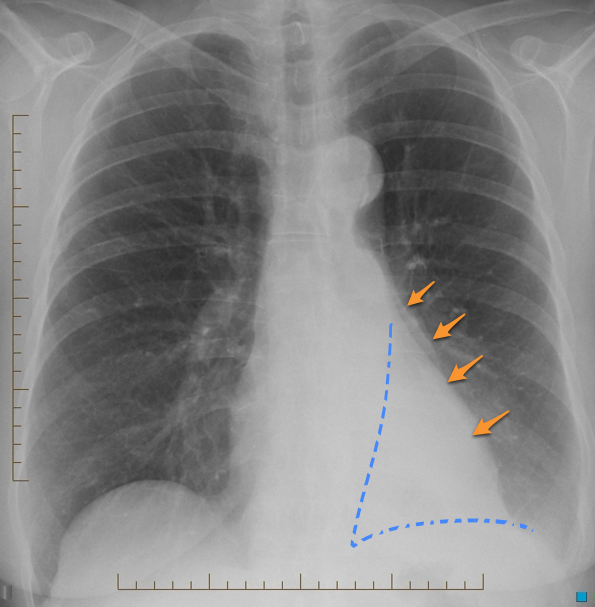

Relaxation (passive) Atelectasis

Caused by relaxation of lung adjacent to an intrathoracic lesion causing mass effect, such as a pleural effusion, pneumothorax, or pulmonary mass. Also known as compressive atelectasis. Causes: most classicaly seen adjacent to a pleural effusion. Could also be seen from adjacent compression of lung from a mass, hiatal hernia, or a large bleb - anything directly pushing on the lung.